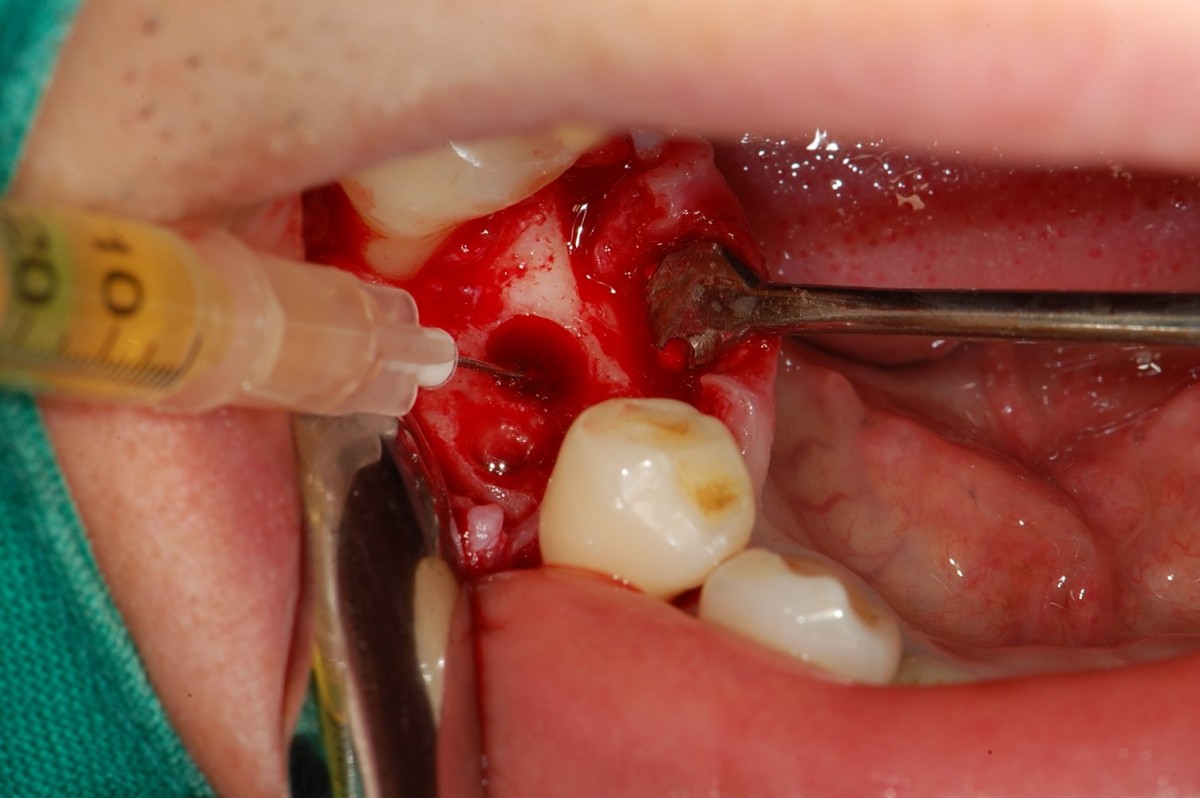

▲Radiograph after impant surgery.